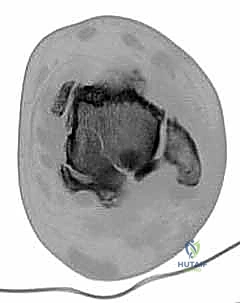

3. استئصال العظام التالفة (Talectomy)

في حالات "شاركو" المتقدمة، تكون عظمة الكاحل (Talus) مجرد فتات عظمي ميت (Avascular Necrosis). يتم استئصال هذه العظمة بالكامل، بالإضافة إلى إزالة أي غضاريف متبقية من أسفل قصبة الساق وأعلى عظمة الكعب لضمان تلامس عظمي حيوي ونظيف.

4. تحضير قصبة الساق وعظمة الكعب

بعد إزالة العظام التالفة، يتم تسوية سطح عظمة قصبة الساق (Tibia) وعظمة الكعب (Calcaneus) بحيث يتطابقان تماماً. هذه الخطوة حاسمة لضمان استقامة القدم (Alignment) وتجنب أي قصر زائد في طول الطرف.